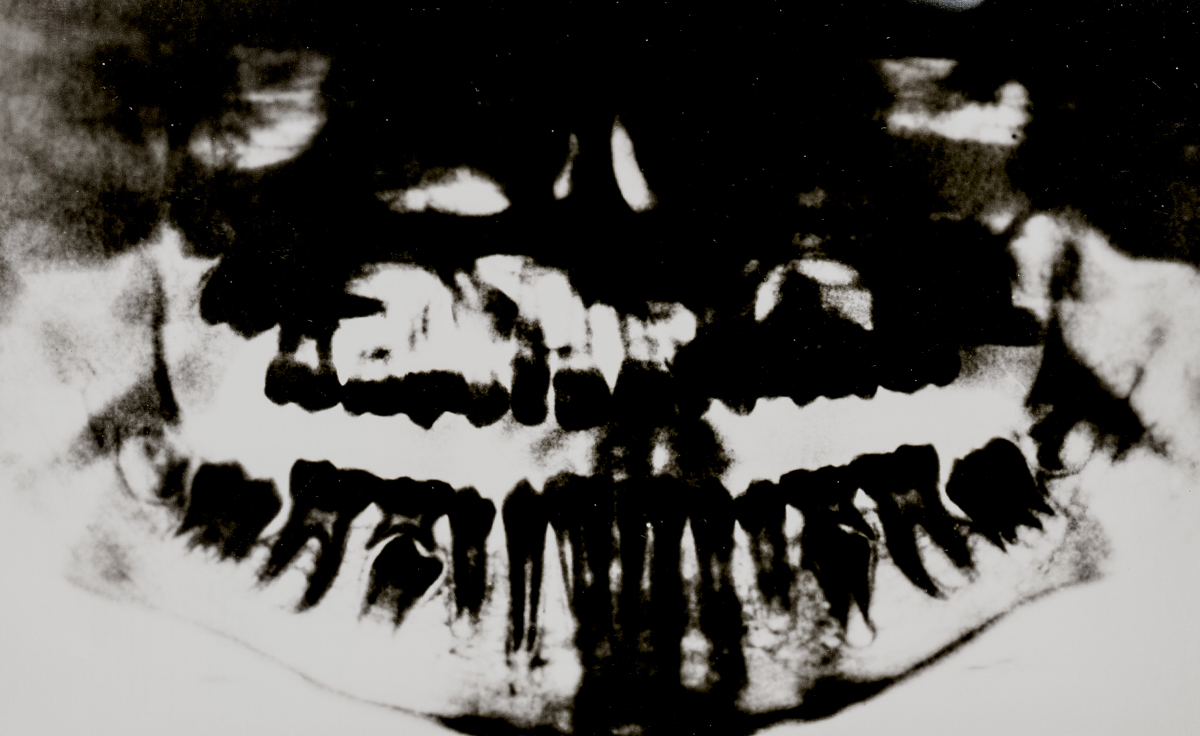

SURFACES SENSIBLES — À la frontière de l'autoportrait, "Surfaces sensibles" retranscrit une partie de ma réalité et brouille les limites entre l'intime anatomique et l'émotionnel.

La science produit les images les plus concrètes et les plus neutres pour illustrer les affects. Pourtant, par leur froideur et leur distance, elles sont les moins aptes à témoigner des émotions. Chaque radiographie, scanner, IRM correspond à une douleur ou à un mal-être spécifique.

Depuis peu, ces images ne sont plus seulement des réminiscences de douleurs passées, mais également des matériaux bruts inspirants pour ma pratique photographique. À partir des radios originelles, j'ai utilisé plusieurs techniques telles que la superposition et le tirage argentique dans le but de me rapprocher d'une perception alternative de ce corps irradié.